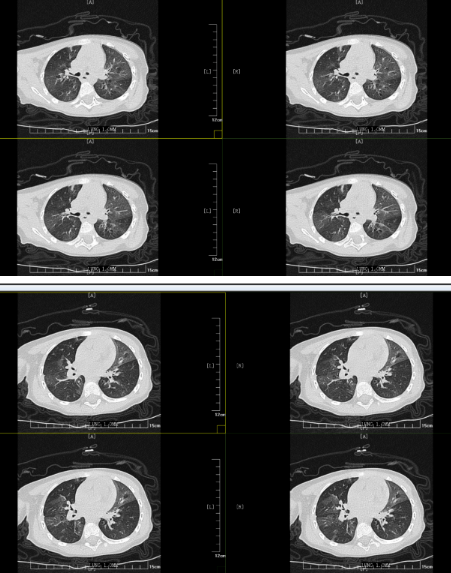

但胸部CT的結(jié)果表明小丸子的肺內(nèi)病變比較重,同時(shí)通氣也不均勻,確實(shí)存在堵塞,可這個(gè)"堵住氣管的東西”到底是什么,還得在支氣管鏡檢查下才能知道。在和小丸子的父母詳細(xì)溝通病情后,入院第二天一早,小兒內(nèi)科田恬主任便為其進(jìn)行了無(wú)痛電子支氣管鏡檢查。